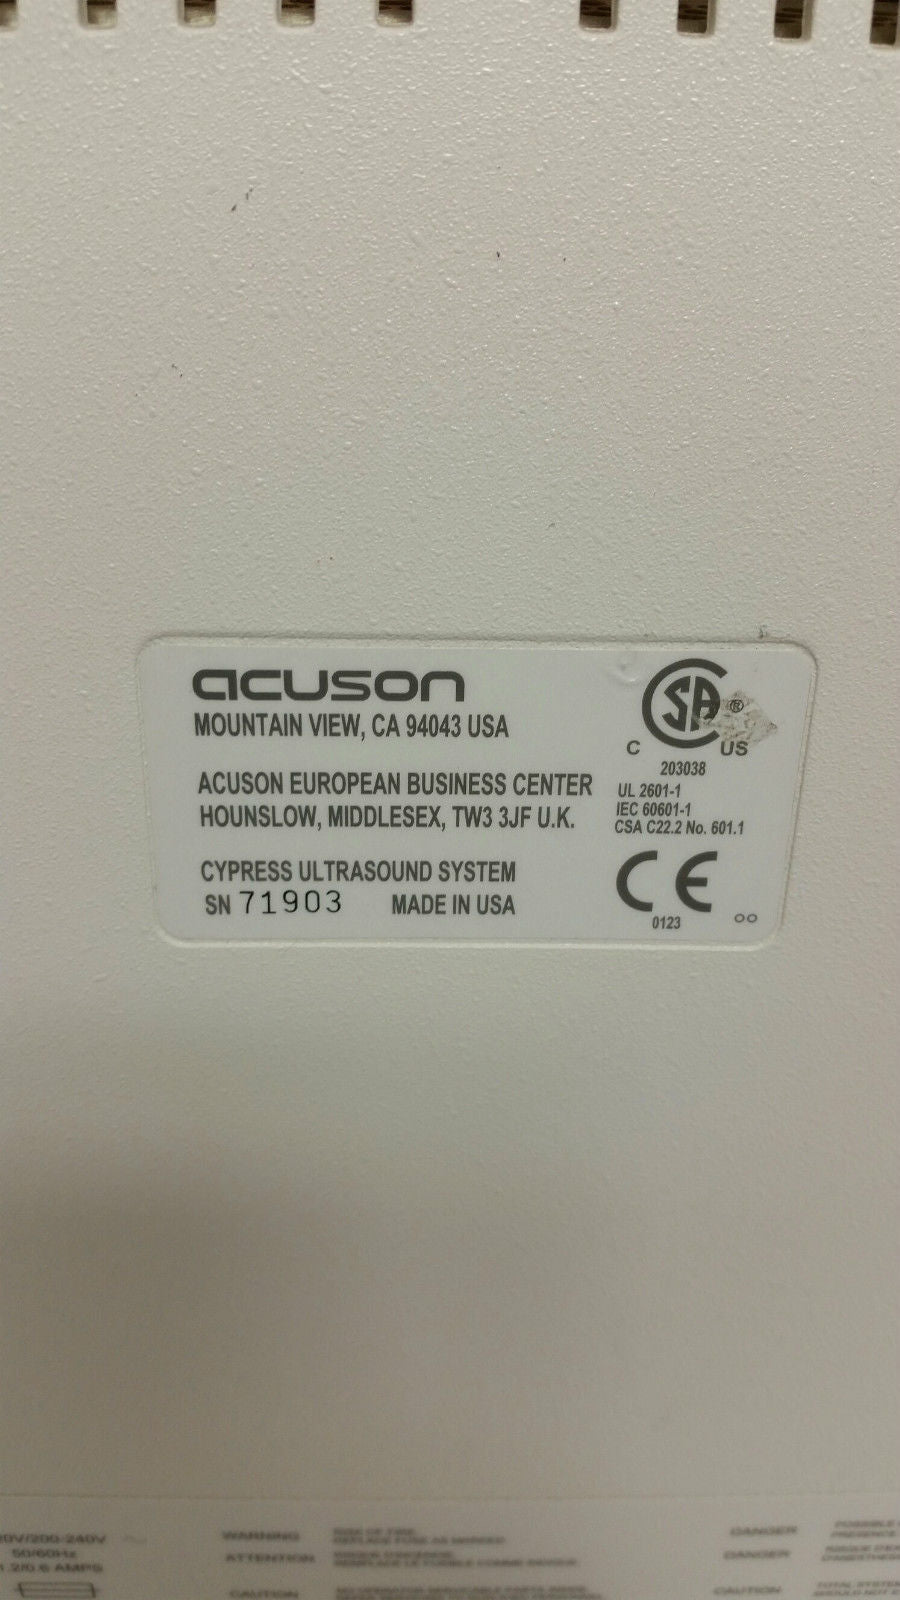

Brand: Acuson

Model: Cypress